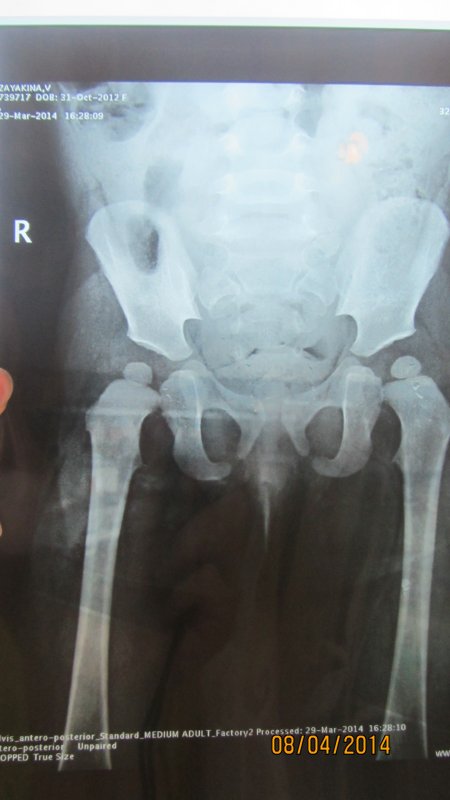

Константин Сергеевич, доброе время суток!!! Очень нужна Ваша консультация!!! Мы просто в отчаянии. Помогите, пожалуйста! Нашей дочки сейчас 1 год и 5 месяцев. В 3 месяца сделали узи т/б суставов- заключение оба сустава-тип Iа. В 6 месяцев пошли на прием к ортопеду: ограничений отведения нет; кожные ягод. и подкол. складки симметр.; длина ног Д=S; ось нижних конечностей правильная, тенденция к вальгусной деформ. стоп.; объем движений в Ш.О.П. полный DS: плосковальгусные стопы. Назначили ЛФК, орторежим, ортообувь с фикс. ГСС. явка в 1 год Мы пришли в 9 месяцев. Нам написали все тоже самое, только добавили мяч и коврик. Явка через пол года. У нас же с 6 месяцев в т/б суставах часто был слышен хруст (щелчек), когда я меняла памперс , однако массажист говорил, что ничего не хрустит (массаж мы делали 5 раз)(массажист у нас врач-хирург) На этом дело и было бы закончено НО!! Хруст все же продолжался. Мы сделали узи т/б суставов в 1,1месяц в НИИТО заключение: признаки задержки темпов оссификации ядер, оба сустава- тип 1а. Затем отправились на консультацию к ортопеду в НИИТО. назначили: ЛФК, массаж, орто обувь, электрофорез, парафин, плавание, Д3 в возростной дозировке, ходьба по коврику, мультитабс малыш кальций 1/4 т. творог, мясо и ренгенография т/б в прямой проекции через 3 месяца. Сходили еще к одному ортопеду, нам сказали ренген делать не обязательно у вас нет дисплазии. Однако мы всеже сделали ренген в НИИТО в 1,5 месяцев и результат по нему такой:- ядра окостенения головок бедренных костей расположены в проекции ацетабулярной впадины, симметричны, децентрированы; - ацетабулярный угол D=28 S=25; -проекционный ШДУ D=156 S=143; - угол наклона плоскости входа во впадину D=37 S=39; - угол Виберга D= 7 S=11; - линии Шентона изломана слева, линии Кальве не нарушены; - симптом Омбреданна отрицательный с обеих сторон. Заключение: Двусторонняя дисплазия тазобедренных сочленений. Помогите, пожалуйста! Что нам делать? Как к Вам можно попасть на прием?? Очень хочется услышать Ваше мнение!

Здравствуйте. Да, дисплазия есть. По тактике лечения - ответил в ЛС. |

нет, рентгенограмма удовлетворительного качества, ошибки нет. Неправильная укладка всегда заметна на снимках. Да, ребенок уложен неидеально, но качество снимка не сильно пострадало, для постановки диагноза достаточно.

Шину носить в течение 6 мес, снимать можно на купание, массаж (хотя, строго говоря, массажу она не мешает), физиопроцедуры. Остальное время она должна надета. Шина центрирует головки бедренных костей в суставных впадинах, при ее ношении происходит правильное формирование тазобедренного сустава, при этом шина не ограничивает движений в коленных суставах и совсем немного-в тазобедренных. Ношение шины - только на голенях, на нижних их третях (не на бедрах!). |